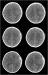

Evidenzbasierte Neurotraumatologie Journal für Neurologie, Neurochirurgie und Psychiatrie 2008; 9 (3): 20-27 Volltext (PDF) Summary Praxisrelevanz Abbildungen Keywords: Neurochirurgie, Neurotraumatologie Evidenzbasierte Medizin bedeutet die individuelle klinische Erfahrung mit der besten verfügbaren Evidenz aus systematischer Forschung zu vereinbaren. In der Neurotraumatologie lassen sich in der Akutphase kaum prospektive randomisierte Studien durchführen. Während der Behandlung von Patienten mit Schädelhirntrauma (SHT) kommt es immer wieder zu alltäglichen Fragestellungen, wie Zeitpunkt des Beginns der Thromboseprophylaxe, antikonvulsive Prophylaxe, Indikation und Art der Hirndruckmessung, Häufigkeit zerebraler CT-Kontrollen, auf die wir uns wissenschaftlich fundierte Antworten wünschen. Ziel dieser Arbeit war es, evidenzbasierte Antworten auf diese Fragen zu finden. Die zu den einzelnen Fragestellungen publizierten Studien wurden in prospektiv-randomisierte, retrospektive Studien und Fallberichte unterteilt. Dementsprechend ließ sich eine Therapierichtlinie bezogen auf spezifische Fragestellungen herausarbeiten. Bei fehlender wissenschaftlicher Grundlage wurden Therapieempfehlungen ausgearbeitet und in einigen Fällen ließ sich nur auf Expertenmeinungen hinweisen. |